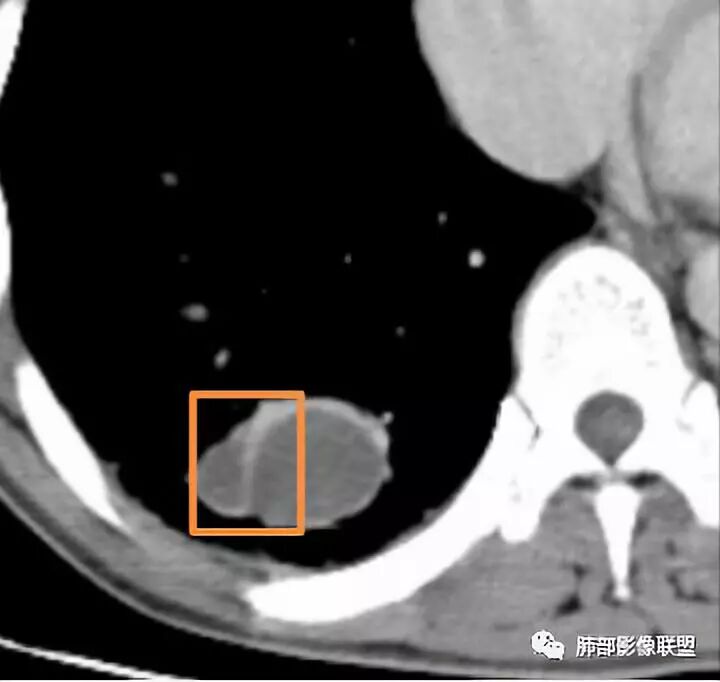

结果

晨读病理

支气管囊肿伴感染

小结

肺内支气管囊肿并感染一般都是囊腔内的感染,这个病例感染灶延续到远端,还伴有肺气肿;猜测是病变压迫近邻支气管造成的慢性炎症;病变以远的肺气肿,或许是活瓣效应。

肺内型支气管囊肿: 在单个肺段,支气管囊肿与支气管闭锁的鉴别比较困难。支气管囊肿应包括支气管闭锁形成的黏液囊肿,因为他们在病理结构上是一样的。但支气管囊肿多不形成周围的肺气肿。支气管闭锁在病理上也常报告为支气管囊肿:因为标本时常垂直于支气管长轴,造成对闭锁段判断困难,闭锁周围的肺组织多不含炭末。但影像上表现的支气管黏液囊肿和周围肺气肿改变可确定先天性支气管闭锁的诊断。